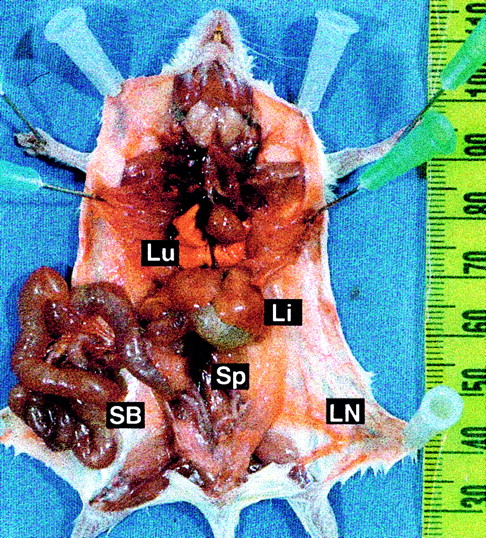

In most mice (13 of 22) given transplants ofTEL-ABL–transduced marrow, a distinct fatal illness developed (Figure 3, open squares). At necropsy, these mice were found to have enlarged, reddened, and distended small intestine; a pale liver; and increased prominence of the vasculature (Figure4). In contrast to mice with CML-like disease, these mice had only slightly elevated PB leukocyte counts and their spleens were minimally enlarged (Figure 4 and Table 1). We named this distinct disease process small-bowel syndrome (SBS). Mice in which SBS developed tended to die earlier, between 23 and 28 days after transplantation, than mice with CML-like disease. Some animals (2 of 22) that were premorbid slightly later clearly died of SBS but had evidence of CML-like disease, with marked splenomegaly and leukocytosis (Figure 3, mixed symbols). This suggests that the 2 diseases can occur independently and that mice that survive the rapid onset of SBS may subsequently have CML-like disease.

Distinctive gross pathological features of TEL-ABL–induced SBS.

Prosected necropsy specimen from a mouse with SBS, showing an enlarged and distended small bowel (SB), pale liver (Li), and increased vascular prominence. The specimen has a lack of lung hemorrhages (Lu), a normal thymus and lymph nodes (LN), and minimal splenomegaly (Sp).